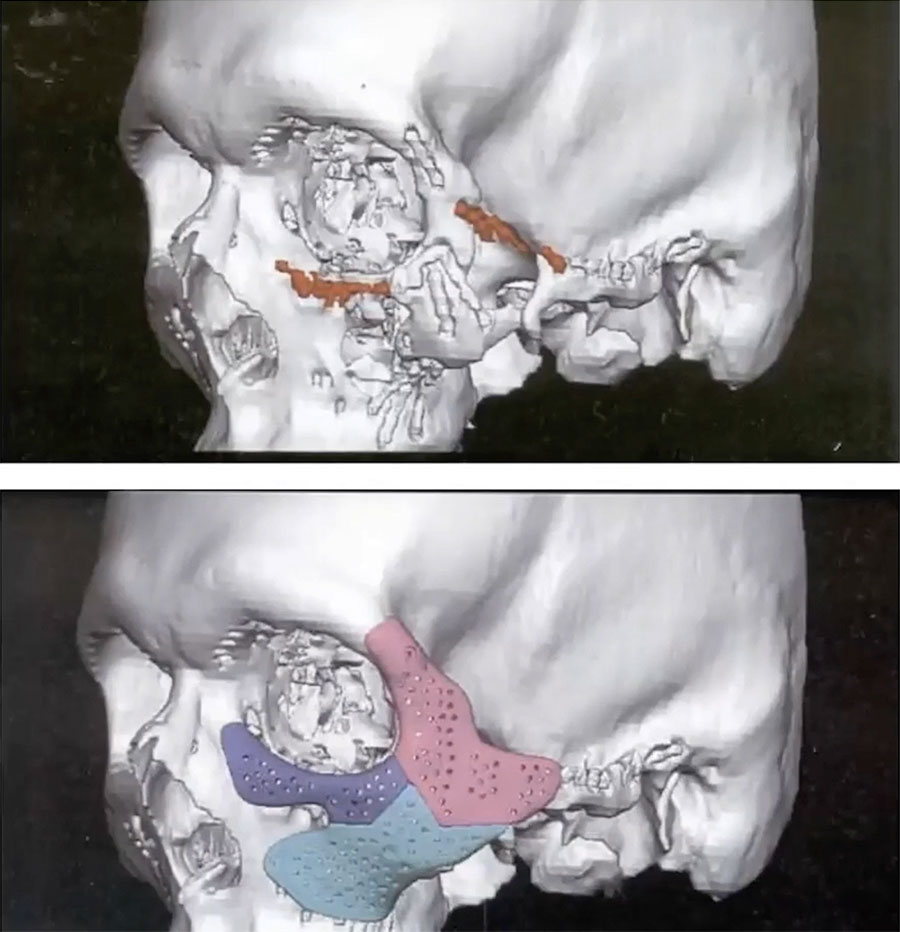

A patient initially presented with class II malocclusion and was referred for orthognathic surgery. However, the patient incurred a ballistic injury to the left zygomatic area prior to the orthognathic surgery and was treated elsewhere. A residual zygomatic defect occurred, and it was decided to defer correction for simultaneous correction with his orthognathic surgery. To resolve both issues, the treatment plan was to perform a sagittal split osteotomy, advancing the mandible, and at the same time augmenting the defect of the left zygoma.

During the initial reconstruction 17 bone plates had been inserted which hindered the ability to perform an osteotomy. After removal of several plates a large three-piece zygomatic patient-matched implant was inserted. The defect in this patient was large, requiring a large implant. A three-piece implant was designed to allow for insertion coronally, intraorally and infra-orbitally. The patient had a successful outcome with stability and functionality still at 10 years postoperatively.